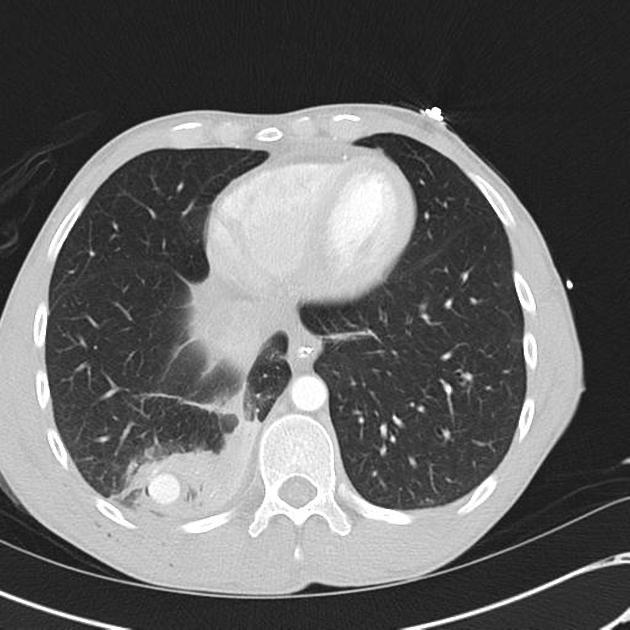

A patient with hx of cystic fibrosis and hemoptysis. What agent is the best treatment agent for the bronchial artery embolization?

permananent particles

A pretty ubiquitous boards question here. Big picture is that you’re treating a field of abnormal tissue; you would not expect to see focal active extravasation. Coils are the classic wrong answer because they would jail you out from future treatments which are likely in these patients with chronic disease processes. Angio of before and after particle embolization: